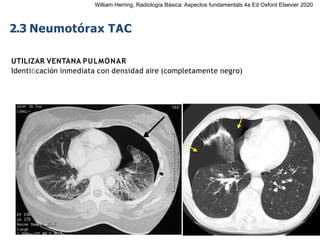

2.3 Neumotórax TAC

UTILIZAR VENTANA PULMONAR

Identificación inmediata con densidad aire (completamente negro)

William Herring, Radiología Básica: Aspectos fundamentals 4a Ed Oxford Elsevier 2020